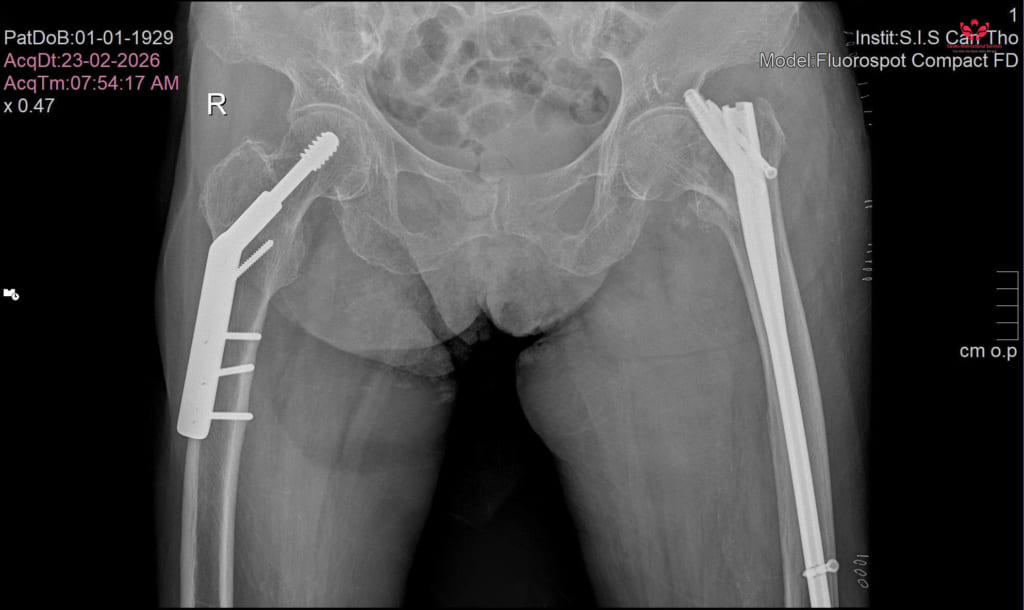

THS.BS Nguyễn Anh Trung – Phó khoa Ngoại tổng hợp Bệnh viện Đa khoa Quốc tế S.I.S Cần Thơ cho biết, kết quả thăm khám và chụp chiếu xác định bệnh nhân bị gãy xương vùng mấu chuyển xương đùi, đây là dạng gãy xương thường gặp ở người lớn tuổi khi té ngã.

Bệnh nhân được phẫu thuật kết hợp xương bằng đinh nội tủy, đây là phương pháp hiện đại giúp cố định xương và phục hồi cấu trúc giải phẫu vùng gãy.

Ca phẫu thuật diễn ra trong khoảng 30 phút dưới gây mê toàn thân. Trong suốt quá trình phẫu thuật, bệnh nhân được theo dõi chặt chẽ các chỉ số sinh tồn như huyết áp, nhịp tim nhằm đảm bảo an toàn tuyệt đối.